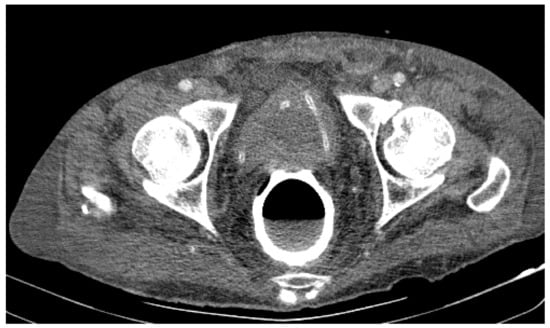

• At the rectal level, the presence of a foreign body is highlighted, with regular edges a maximum diameter of 65 mm (Figure 7 and Figure 8).

Figure 7. Patient’s computer tomography: the presence of a foreign body is highlighted.

Figure 8. Patient’s computer tomography: the presence of a foreign body is highlighted, with regular edges and a maximum diameter of 65 mm.